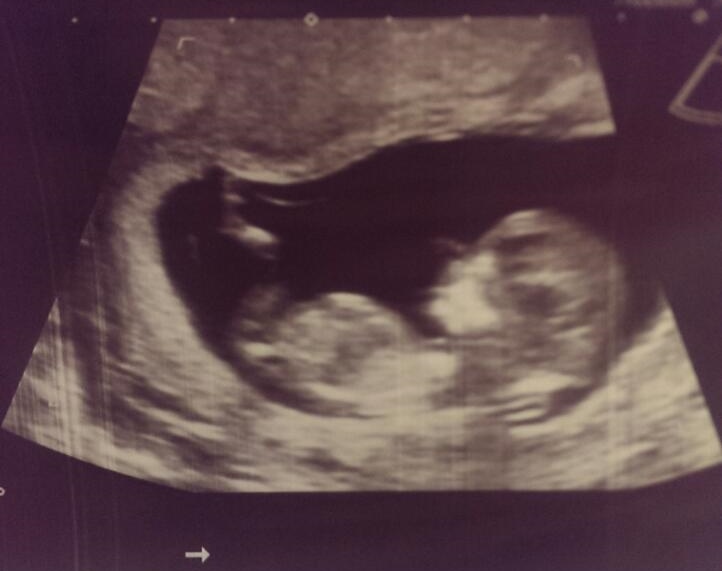

15+5 with #3 after 2 beautiful boys,

nervous to find out gender today eek! Any last guesses?Attachment 24226

well its a boy! lol